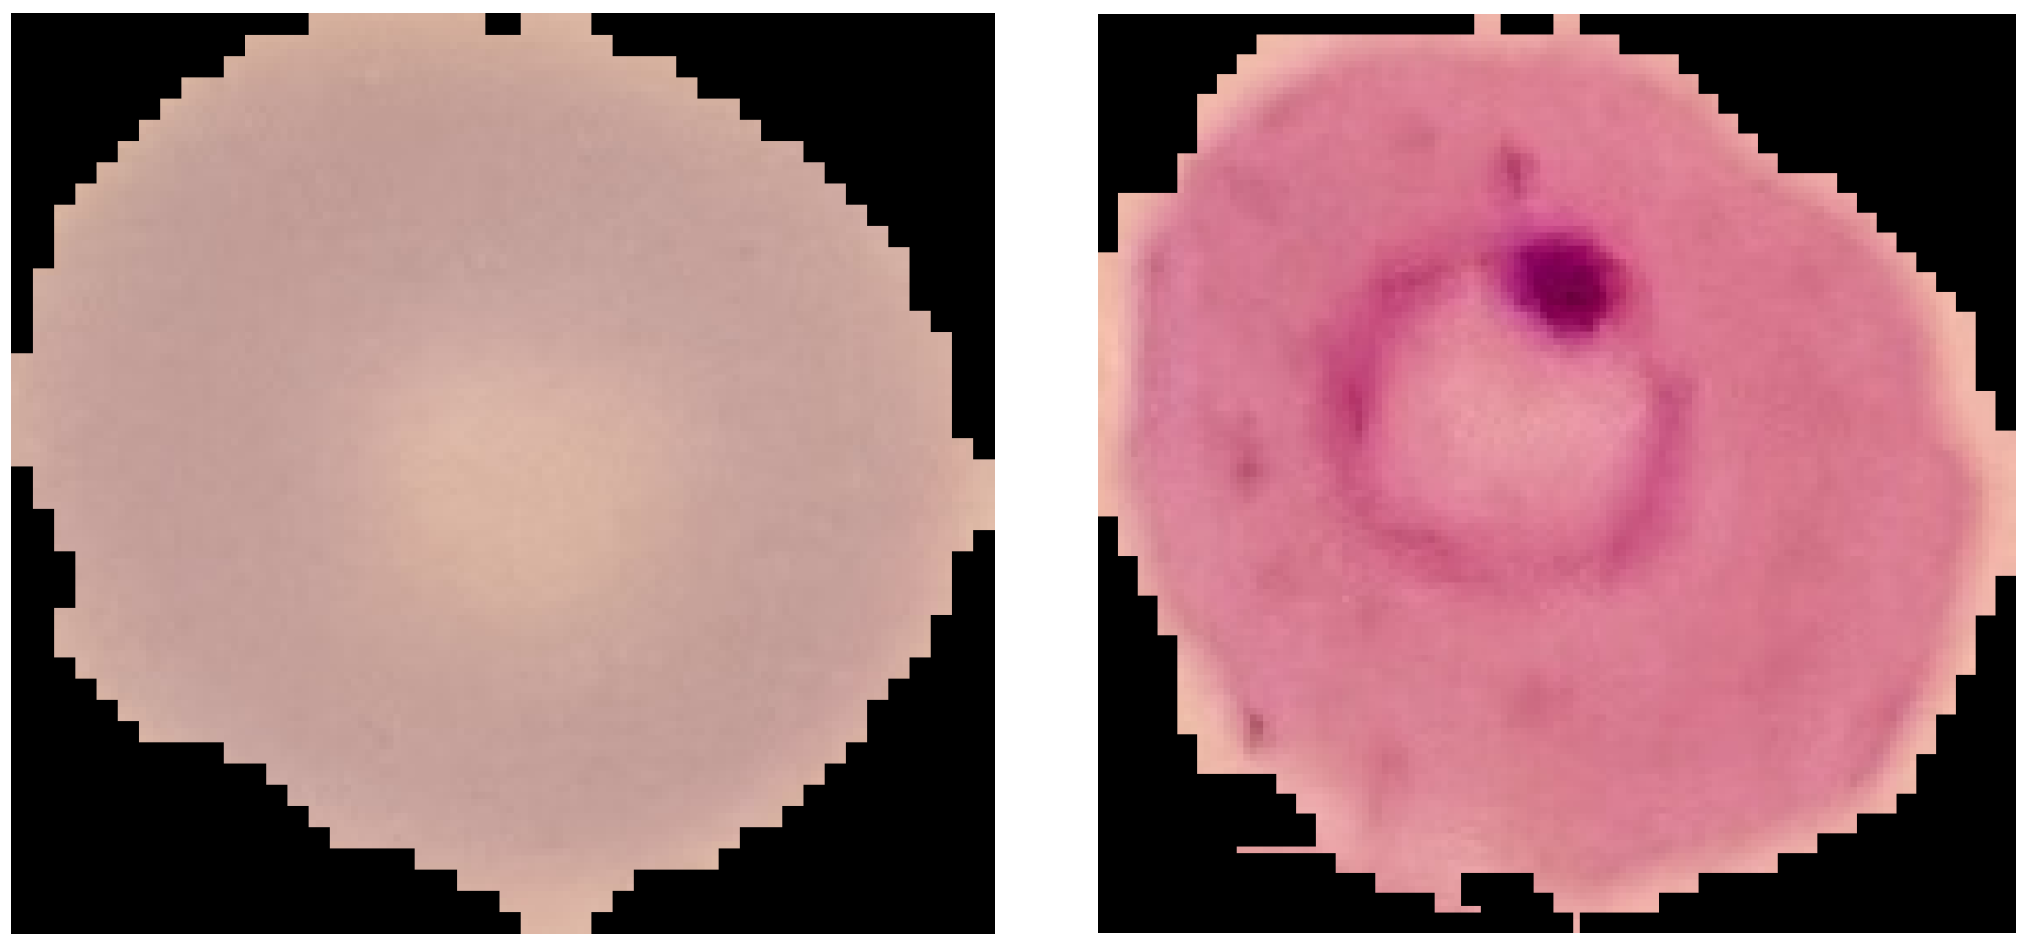

3.1. Datasets

3.1.1. NIH

3.1.2. MP-IDB